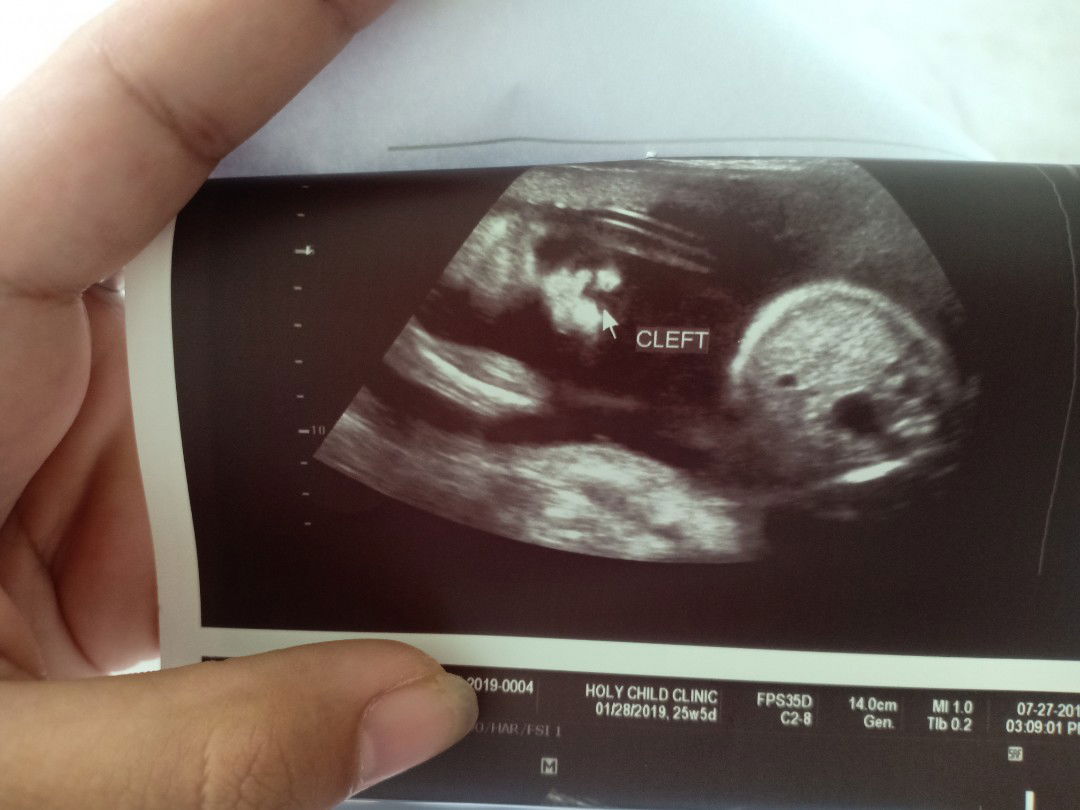

Hi mga mamsh, may chance po bang magkamali yung ultrasound report ni baby? Based on ultrasound po kasi cleft lip siya. Im 24 weeks and 5 days pregnant po. Thanks in advance.

masyado pong klaro yung cleft pero sana mali lang talaga si ob ng tingin, if ever talaga cleft si baby dapat ready kayo at hanap kayo saan maganda paoperahan si baby mas maaga maagapan mas maganda resulta.

May cleft lip po ba talaga baby ko mhie,sabi ng doctor ko nong nagpa ultrasound ako meron dw siyang cleft lip

May margin of error naman ang utz. CAS na ba yung ginawa? If papaulit mo, better sa experienced OB sono.